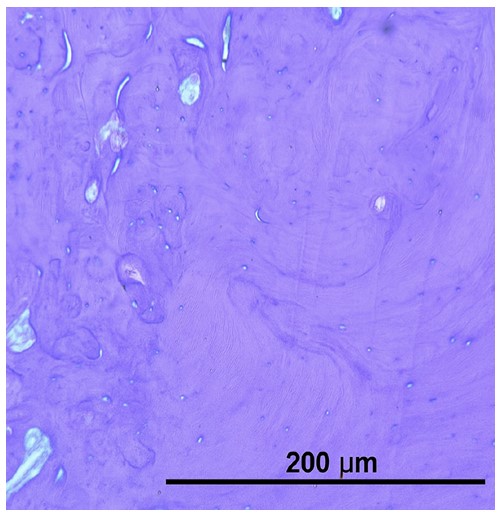

Histological examination revealed complete replacement of normal bone structure with a sclerotic osseous mass, including detectable Haversian systems. The diagnosis of idiopathic osteosclerosis was confirmed based on clinical, radiological, and histological findings (Fig. 2).

Histological examination of the radiopaque lesion confirming the diagnosis of osteosclerosis.

The first case demonstrated successful osseointegration despite the presence of IO, with favorable stability values observed during follow-up examinations. This outcome suggests that dense sclerotic bone may not necessarily contraindicate implant placement, provided appropriate surgical techniques are employed [20, 21]. The high insertion torque achieved during placement and subsequent increase in resonance frequency analysis values indicate that the mechanical properties of sclerotic bone can, in some cases, contribute to favorable primary stability [21, 22]. However, the biological behavior of such bone remains questionable, as the reduced vascularity typical of sclerotic lesions might theoretically compromise the healing response [23-25]. The histological findings in this case, showing replacement of normal bone architecture with dense lamellar bone containing Haversian systems, confirm the diagnosis while highlighting the structural differences from normal alveolar bone [22, 26].

The first case demonstrated successful osseointegration despite the presence of IO, with favorable stability values observed during follow-up examinations. This outcome suggests that dense sclerotic bone may not necessarily contraindicate implant placement, provided appropriate surgical techniques are employed [20, 21]. The high insertion torque achieved during placement and subsequent increase in resonance frequency analysis values indicate that the mechanical properties of sclerotic bone can, in some cases, contribute to favorable primary stability [21, 22]. However, the biological behavior of such bone remains questionable, as the reduced vascularity typical of sclerotic lesions might theoretically compromise the healing response [22, 26, 27]. The histological findings in this case, showing replacement of normal bone architecture with dense lamellar bone containing Haversian systems, confirm the diagnosis while highlighting the structural differences from normal alveolar bone [22, 26].